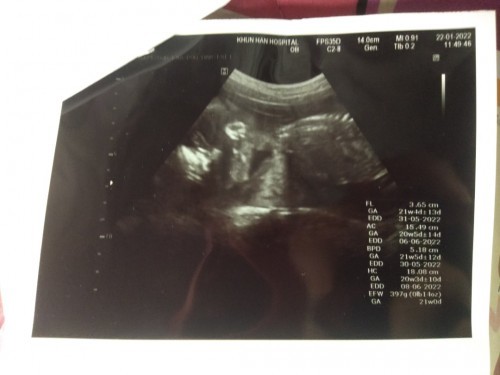

สาวน้อยของแม่ 21 week แล้วค่ะ